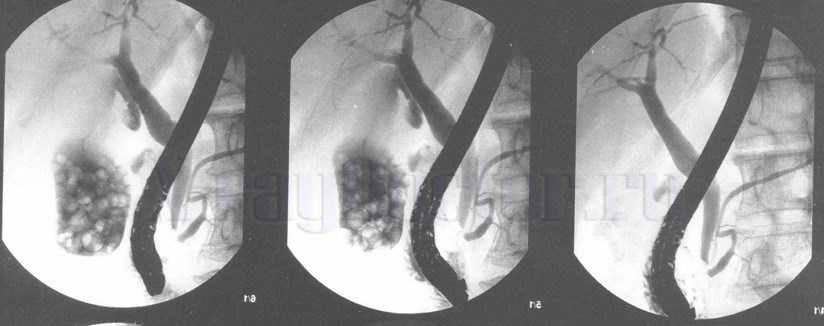

Фото. Ретроградная эндоскопическая холангиография (РЭХГ) (контрастированы желчные и панкреатические протоки, отмечается множество конкрементов)

Исследование оказывается незаменимым при необходимости оперативного лечения заболеваний печени. Оно применяется в качестве основного метода визуализации состояние желчных протоков и 12-перстной кишки при подозрении на опухолевые образования.